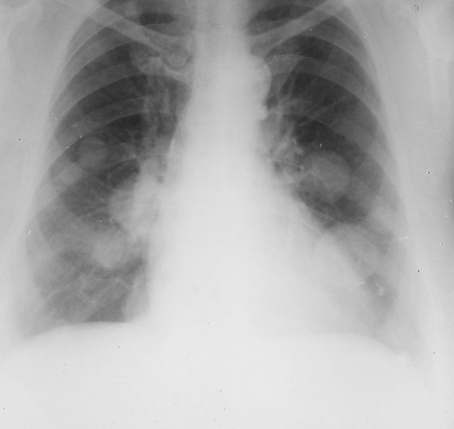

Rx toracică, incidență P-A

DESCRIERE:

pe tot teritoriul pulmonar, bilateral → opacități nodulare multiple de dimensiuni variabile, intensitate medie-mare, omogene, cu contur net

distribuție anarhică

blocuri adenopatice la niv. hilurilor pulmonare

DX: MTS pulmonare hematogene

DD:

hidatidoză - dimensiuni mai mari

bronhopneumonie - contur neregulat, neomogene, distribuție bazală